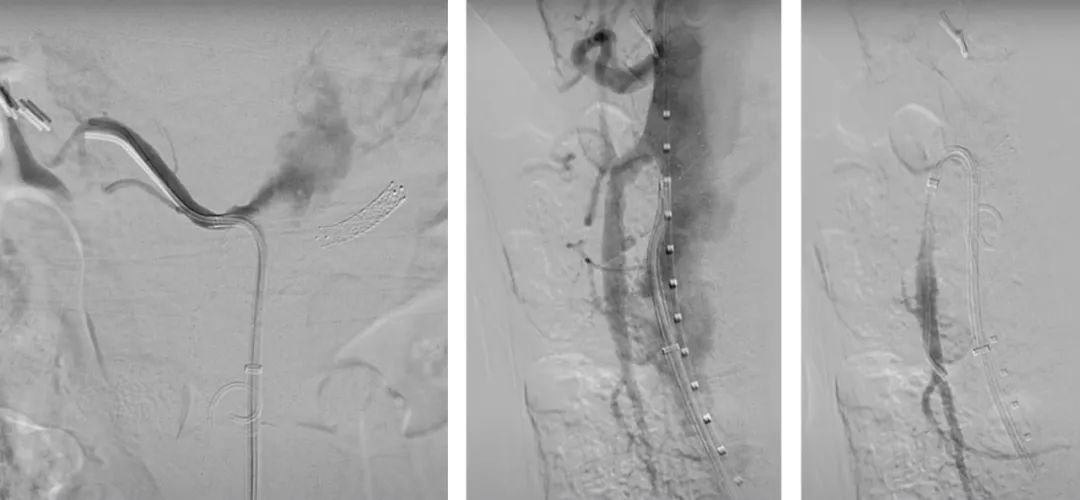

最后进行内脏动脉部分主动脉造影。注意在肾下有足够的空间(约5cm)以植入后续支架。使用普通EVAR支架完成后续的工作。

最后的正/侧位造影显示瘤腔隔绝满意,支架形态良好,主髂动脉及内脏分支动脉血流通畅。术中内脏动脉的总缺血时间<60min,肠系膜上动脉通畅在10-15min以内。

术后即刻造影